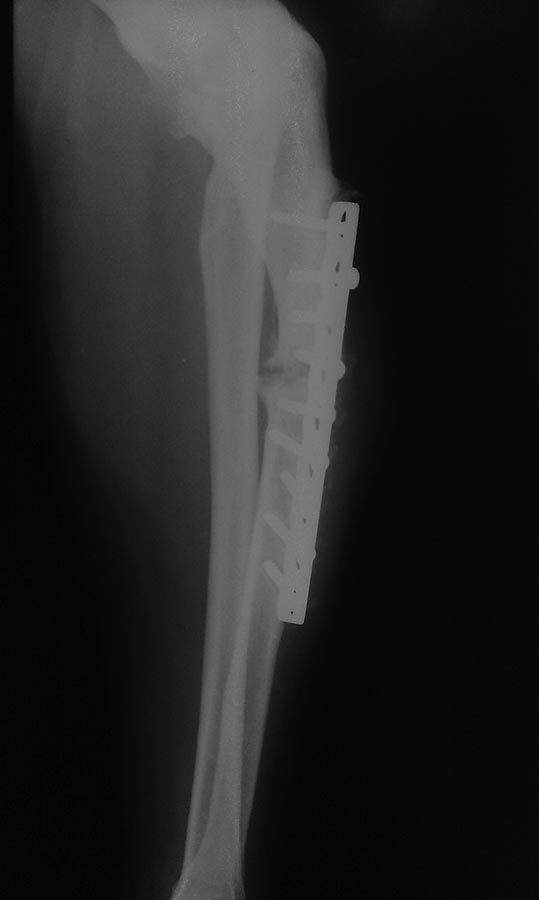

Больной 60 лет. Травма 12 лет назад - перелом локтевой кости.

В одной из клиник выполнен остеосинтез пластиной. Из анамнеза - 2

операции за 3 дня. Все 12 лет боли и деформация. На представленных

рентгенограммах резорбция вокруг всех винтов, деформация. Предполагается

длинная LCP пластина и костная пластика. Интересно Ваше мнение, коллеги.